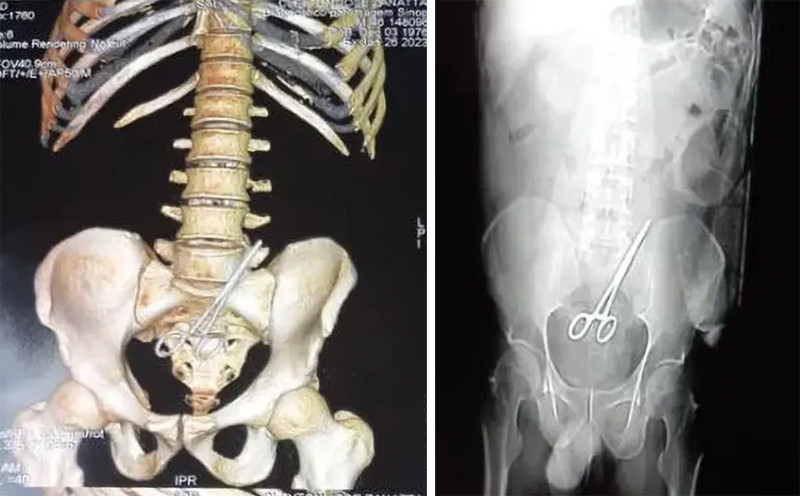

Bác sĩ phẫu thuật người Brazil đã bỏ quên chiếc kéo trong cơ thể một chính trị gia địa phương khi phẫu thuật. Ông Cleyton Jose Zanatta, Ủy viên hội đồng thành phố Nova Santa Helena ở bang Mato Grosso (Brazil) hôm 20/1, tới một bệnh viện gần đó để cắt bỏ khối u trong ruột.

Tuy nhiên, vị chính trị gia cảm thấy có điều gì đó không ổn khi ốm mệt suốt 6 ngày sau ca phẫu thuật. Thành viên Đảng Dân chủ Xã hội Brazil đã trở lại bệnh viện trên để kiểm tra.

Hình ảnh cho thấy kéo nằm trong cơ thể của ông Zanatta. Ảnh: New York Post

Theo New York Post, kết quả chụp CT ghi nhận, trong bụng của ông Zanatta có một chiếc kéo. Báo cáo cho biết các bác sĩ đã để quên dụng cụ cắt chỉ bên trong người bệnh nhân khi khâu vết thương cho ông. Sau đó, ê-kíp phẫu thuật lấy chiếc kéo ra khỏi bụng của ông Zanatta. Người bệnh đã bình phục sau sự cố y tế và đang trong tình trạng ổn định.

Ông Zanatta đã phải phẫu thuật lần thứ 2 để lấy chiếc kéo ra. Ảnh: New York Post